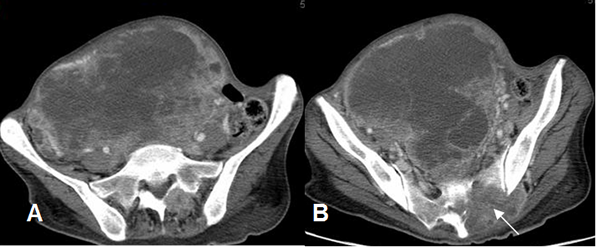

Fig 219. Leiomiosarcoma.

A y B: TAC axial. Gran lesión heterogénea en el retroperitoneo, por leiomiosarcoma.

En B hay lesión lítica del sacro.